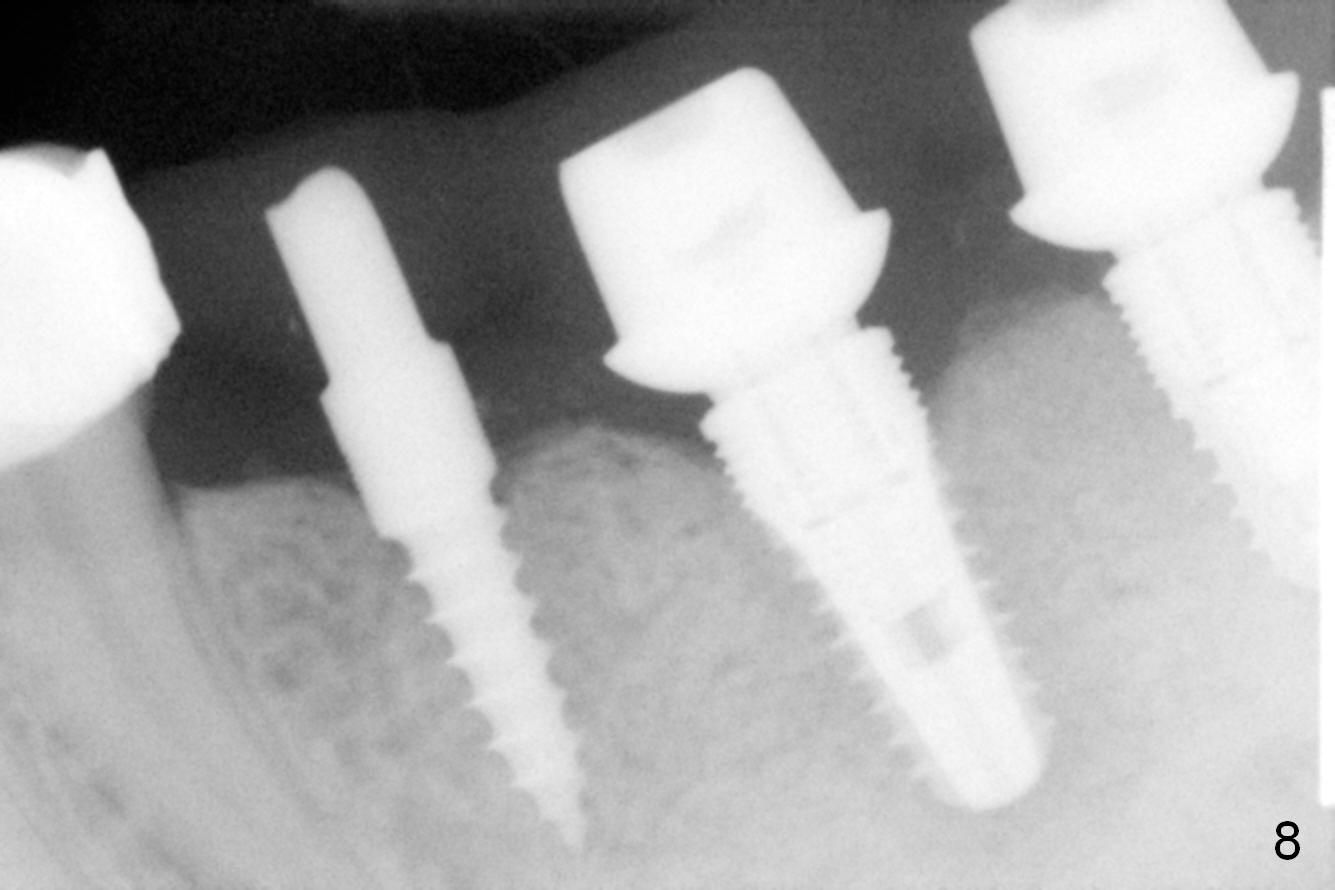

The patient is doing well postop, but 1 month postop, she complains of pain in the left submandibular area. When the immediate provisional is removed, the gingiva between the implants is erythematous (Fig.5 ^). The provisional is modified with accentuated grooves between the margins of the implants (Fig.6 *) with oral hygiene instruction. In fact the provisional is not cemented so that it is easy for self cleansing. There is crestal bone resorption 3 months postop (Fig.7,8). No further bone loss 1 year post cementation (Fig.9, cropped from pan). The bone density around the implants increases 2 years 8 months post cementation (Fig.10).